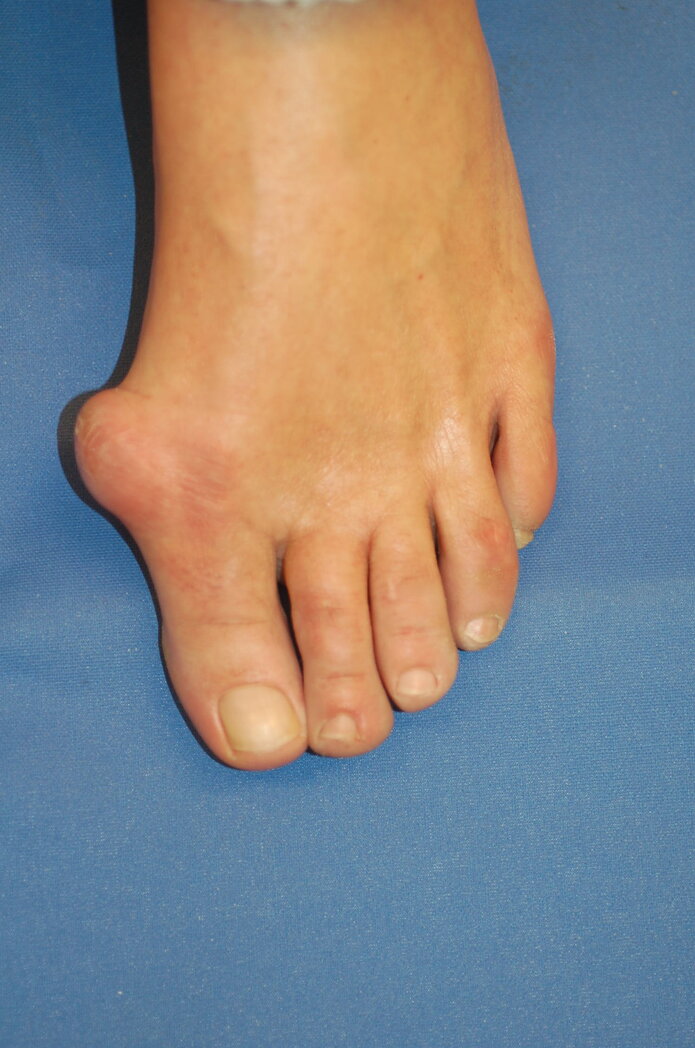

Beim Hallux valgus handelt es sich um die häufigste Fehlstellung des Vorfußes und der Zehen. Während bei einem gesunden Fuß die Zehenknochen gerade ausgerichtet sind, neigt sich bei einem Hallux valgus das Grundgelenk der Großzehe nach außen. Durch diese Abspreizung des ersten Mittelfußknochens wird der Fuß breiter. An seiner Innenseite wird eine mehr oder weniger große und charakteristische Wölbung am Großzehengrundgelenk sichtbar. Unbehandelt verändert die Großzehe zunehmend ihre Ausrichtung und schiebt sich über oder unter die Kleinzehen. Sie verdrängt diese aus ihrer natürlichen Position, was zu weiteren Fußdeformitäten führt.